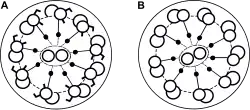

| Normal cilia (A) and cilia representative of Kartagener's syndrome (B) | |

Primary ciliary dyskinesia (PCD) is a rare, autosomal recessive genetic ciliopathy, that causes defects in the action of cilia lining the upper and lower respiratory tract, sinuses, Eustachian tube, middle ear, fallopian tube, and flagella of sperm cells. The alternative name of "immotile ciliary syndrome" is no longer favored as the cilia do have movement, but are merely inefficient or unsynchronized. When accompanied by situs inversus the condition is known as Kartagener syndrome.[3]